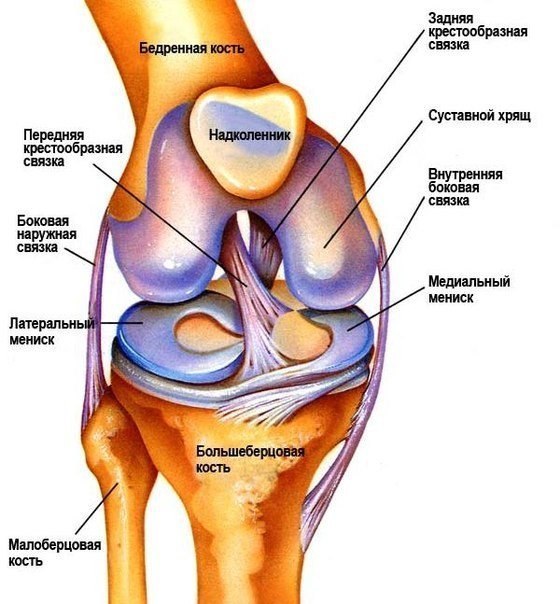

Проблемы заболеваний суставов в спорте сводятся к истиранию хрящевой ткани, покрывающей скользящие поверхности суставов. Вообще — то, хрящи сами по себе очень прочны, а потому истирание постигает суставы где — то глубоко за семьдесят. Однако когда вы, к примеру, приседаете с тяжелой штангой, вес отягощения «припечатывает»суставные поверхности друг к другу с силой, на которую природа не рассчитывала.Трение внутри коленного сустава многократно возрастает, отсюда и берется преждевременное истирание.

Профилактика этого явления сводится к приему препаратов, препятствующих истиранию или восстанавливающих состоявшиеся повреждения.

Это еще один «строительный блок» в составе хрящевой ткани. Молекула хондроитина несет с собой воду, а это крайне важно для благополучной жизнедеятельности хрящей. Как известно, в хрящах отсутствуют капилляры, которые могли бы питать их необходимыми веществами, в том числе водой. Ну а если хрящи теряют воду, они становятся менее износостойкими. Прием хондроитина в виде пищевой добавке будет крайне полезен в период тяжелых тренировок.